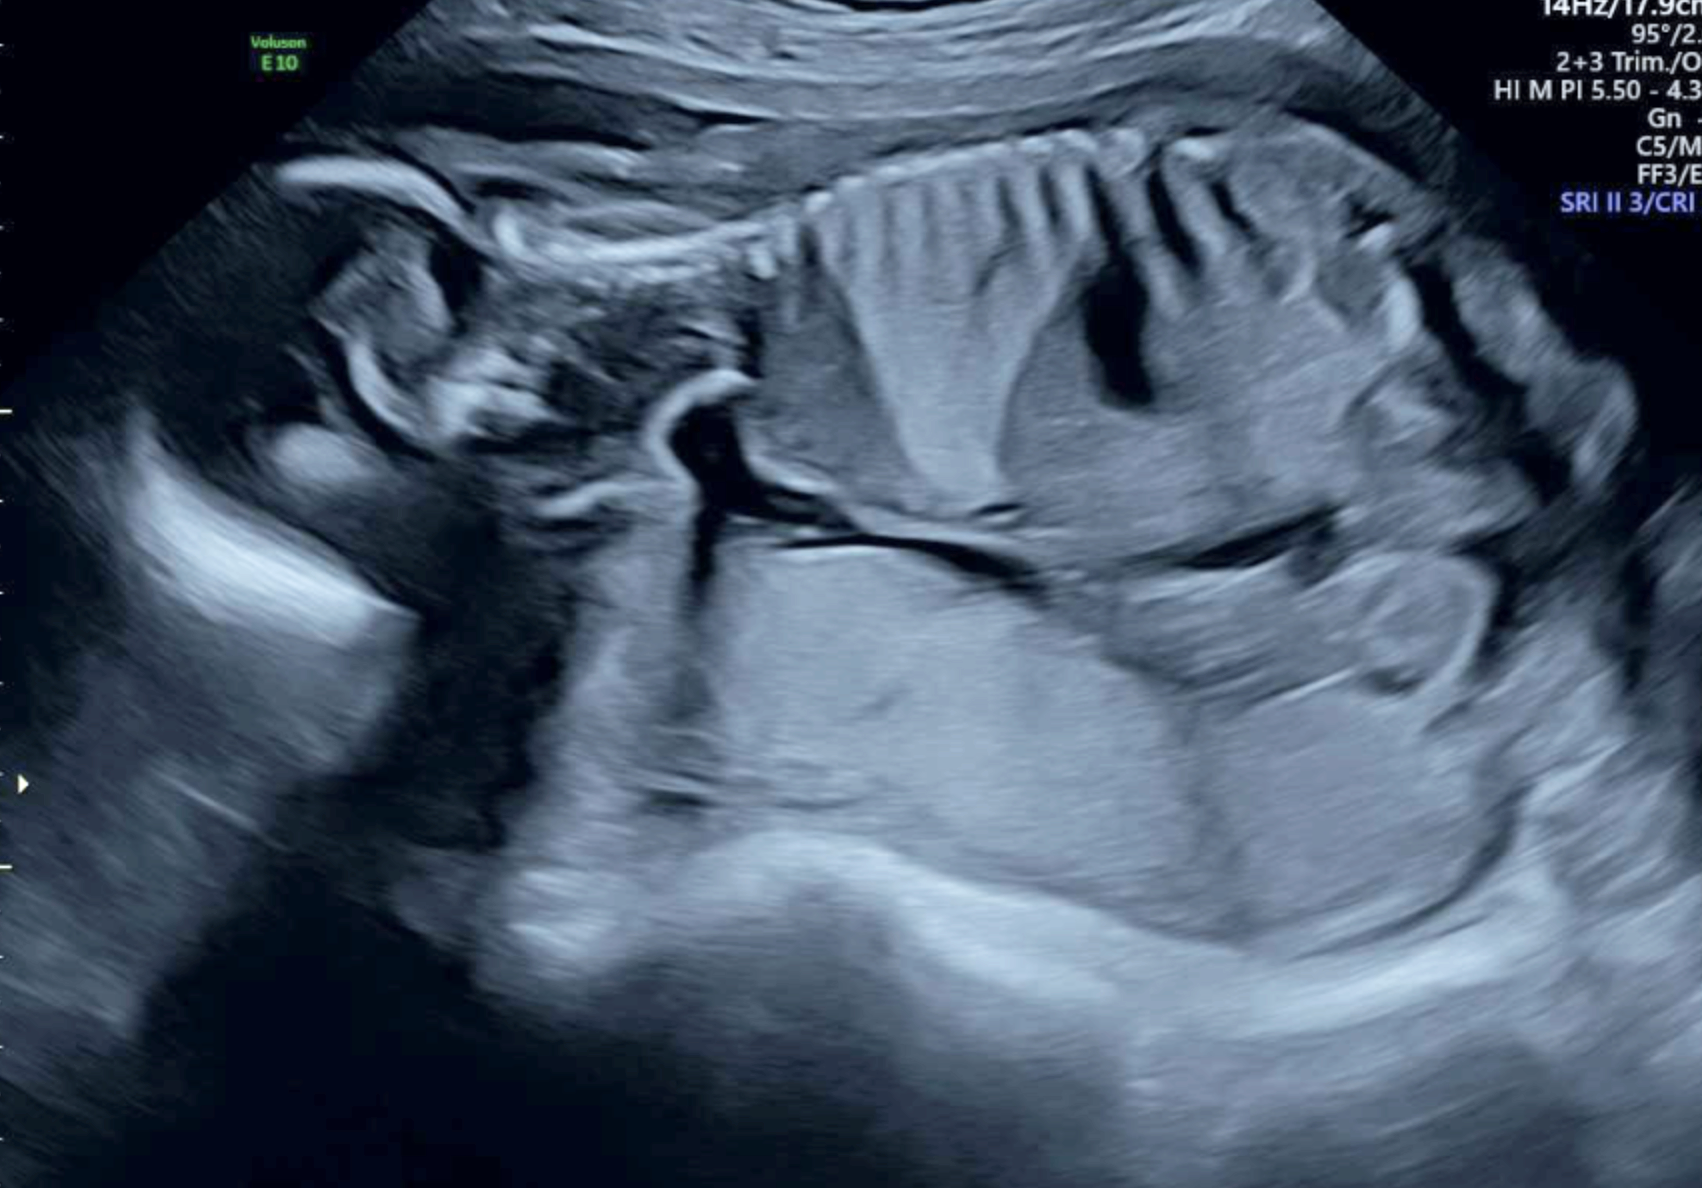

The bright wedge shape on this ultrasound is a lung malformation. This baby was diagnosed with a bronchopulmonary sequestration (BPS).